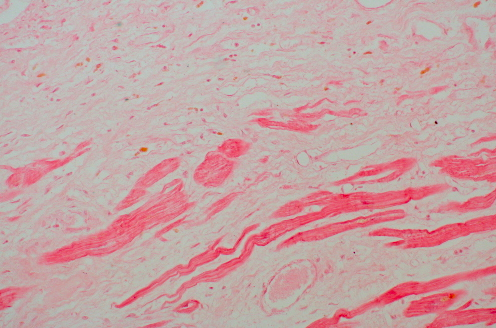

9

Q

What do you see?

A

- Myocardium shown demonstrates pale fibrosis with collagenization following healing of a myocardial infarction. There is minimal cellularity; a few remaining viable red myocardial fibers are present

- This stage is reached about 2 months following the initial ischemic event. This collagenous scar is nonfunctional for contraction and will diminish the ejection fraction

- Such a scar will not rupture